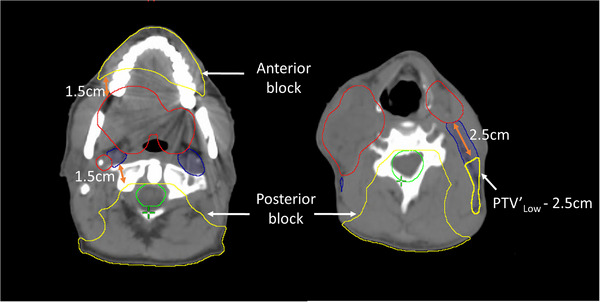

Additional structures and goals were introduced to control undesired hotspots in PTV high, medium and low, such as V105% ≤ 5% with intermediate priority, as well as additional goals (D0.03cc ≤ 105% and V105% ≤ 5%) to cropped structures of PTVMed, Low defined as follow: PTVMed and/or PTVLow were cropped a certain distance from PTVHigh. This distance was determined based on the prescription dose to PTVMed and/or PTVLow relative to the prescribed dose to PTVHigh. This distance was either 1.5 or 2.5 cm away from PTVHigh for prescribed doses of 90% or 80% relative to that of PTVHigh, respectively (Table 2). To limit hotspots outside of the targets, additional cropped body structures from all PTVs were created and assigned a goal of D0.03cc < PTVHigh prescription dose. Anatomically‐derived helper structures for isodose shaping, such as low dose in the posterior neck and oral cavity, were defined with lower priority goals (Table 2). For the posterior block, a margin around the union of the brainstem and the spinal cord was taken 9 cm laterally and posteriorly with the resulting structure then cropped 1.5 cm away from the target. For the anterior block, the oral cavity was cropped 1.5 cm away from the target. It is critical to note that the above helper structures must be anatomically derived (i.e., not edited manually as is common practice in more standard optimization‐based planning approaches) so that these helper structures adapt appropriately during the oART process (Figure 1).

FIGURE 1.

Illustration of the anatomically‐derived helper structures described in Table 2 for isodose shaping and hotspot control. PTVHigh (red), PTVLow (blue), union of brainstem and spinal cord PRVs (green), and anatomically‐derived helper structures (yellow).